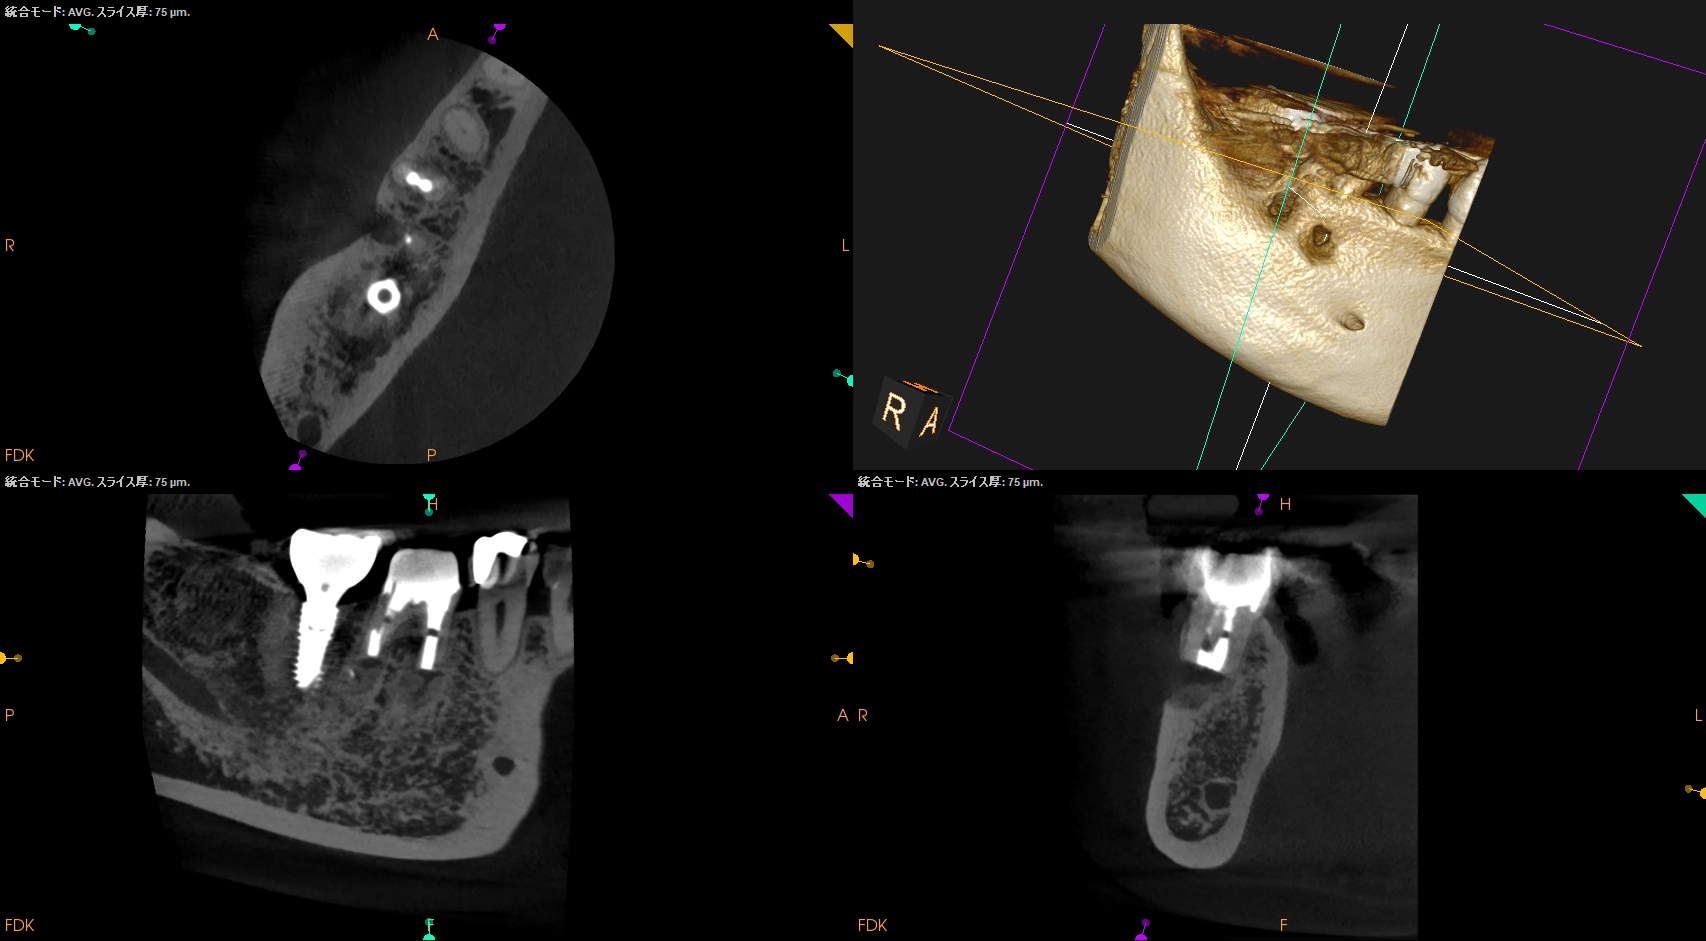

Apicoectomy時にはApexの位置を正確に把握する必要がある臨床的理由〜#30 Crown, Post Core removal⇨M,D Apicoectomy 1回法

治療から5ヶ月が経過していた。

#30 M,D Apicoectomy 5M recall(2026.3.30)

B

外科直後と比較した。

最終補綴もOKだ。